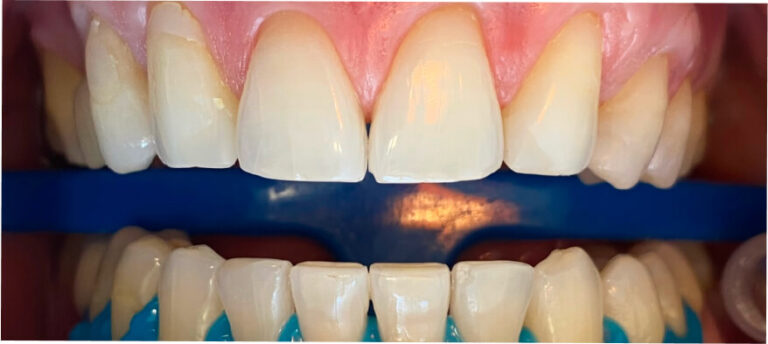

Po

Higienizacja